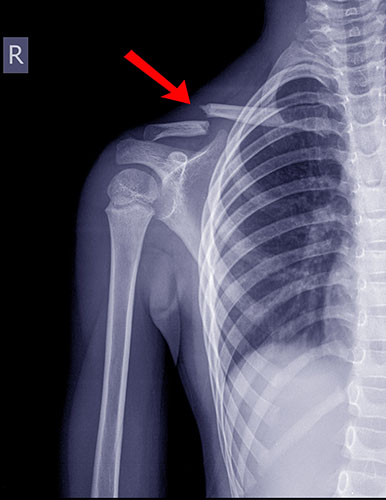

Τραυματολογία

- Κατάγματα

Κατάγματα